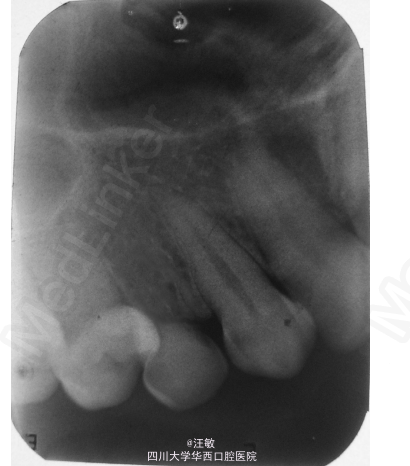

检查发现22牙缺失,23牙处于22牙位置,左上乳尖牙滞留。所有的咬合关系都正常。

计划拔除左上滞留乳尖牙,拔除后可考虑活动或固定修复。由于经济等问题患者选择固定桥修复,以23、24为基牙修复缺牙间隙。